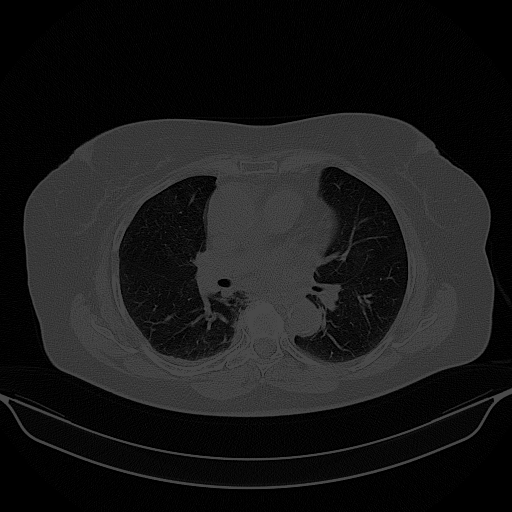

Targeted Slice 70 - Network-Normalized Analysis (Generated vs Real Venous)

0.836

SSIM Score

0.119

RMSE

0.052

MAE

Average Network-Normalized Metrics Across All Slices (161 slices) - Generated vs Real Venous

0.838

SSIM Score (Avg)

0.111

RMSE (Avg)

0.050

MAE (Avg)

Targeted Slice 70 - HU-Space Analysis (Generated vs Real Venous)

HU SSIM

119.3

HU RMSE

52.3

HU MAE

Average HU-Space Metrics Across All Slices (161 slices) - Generated vs Real Venous

HU SSIM (Avg)

110.7

HU RMSE (Avg)

50.1

HU MAE (Avg)